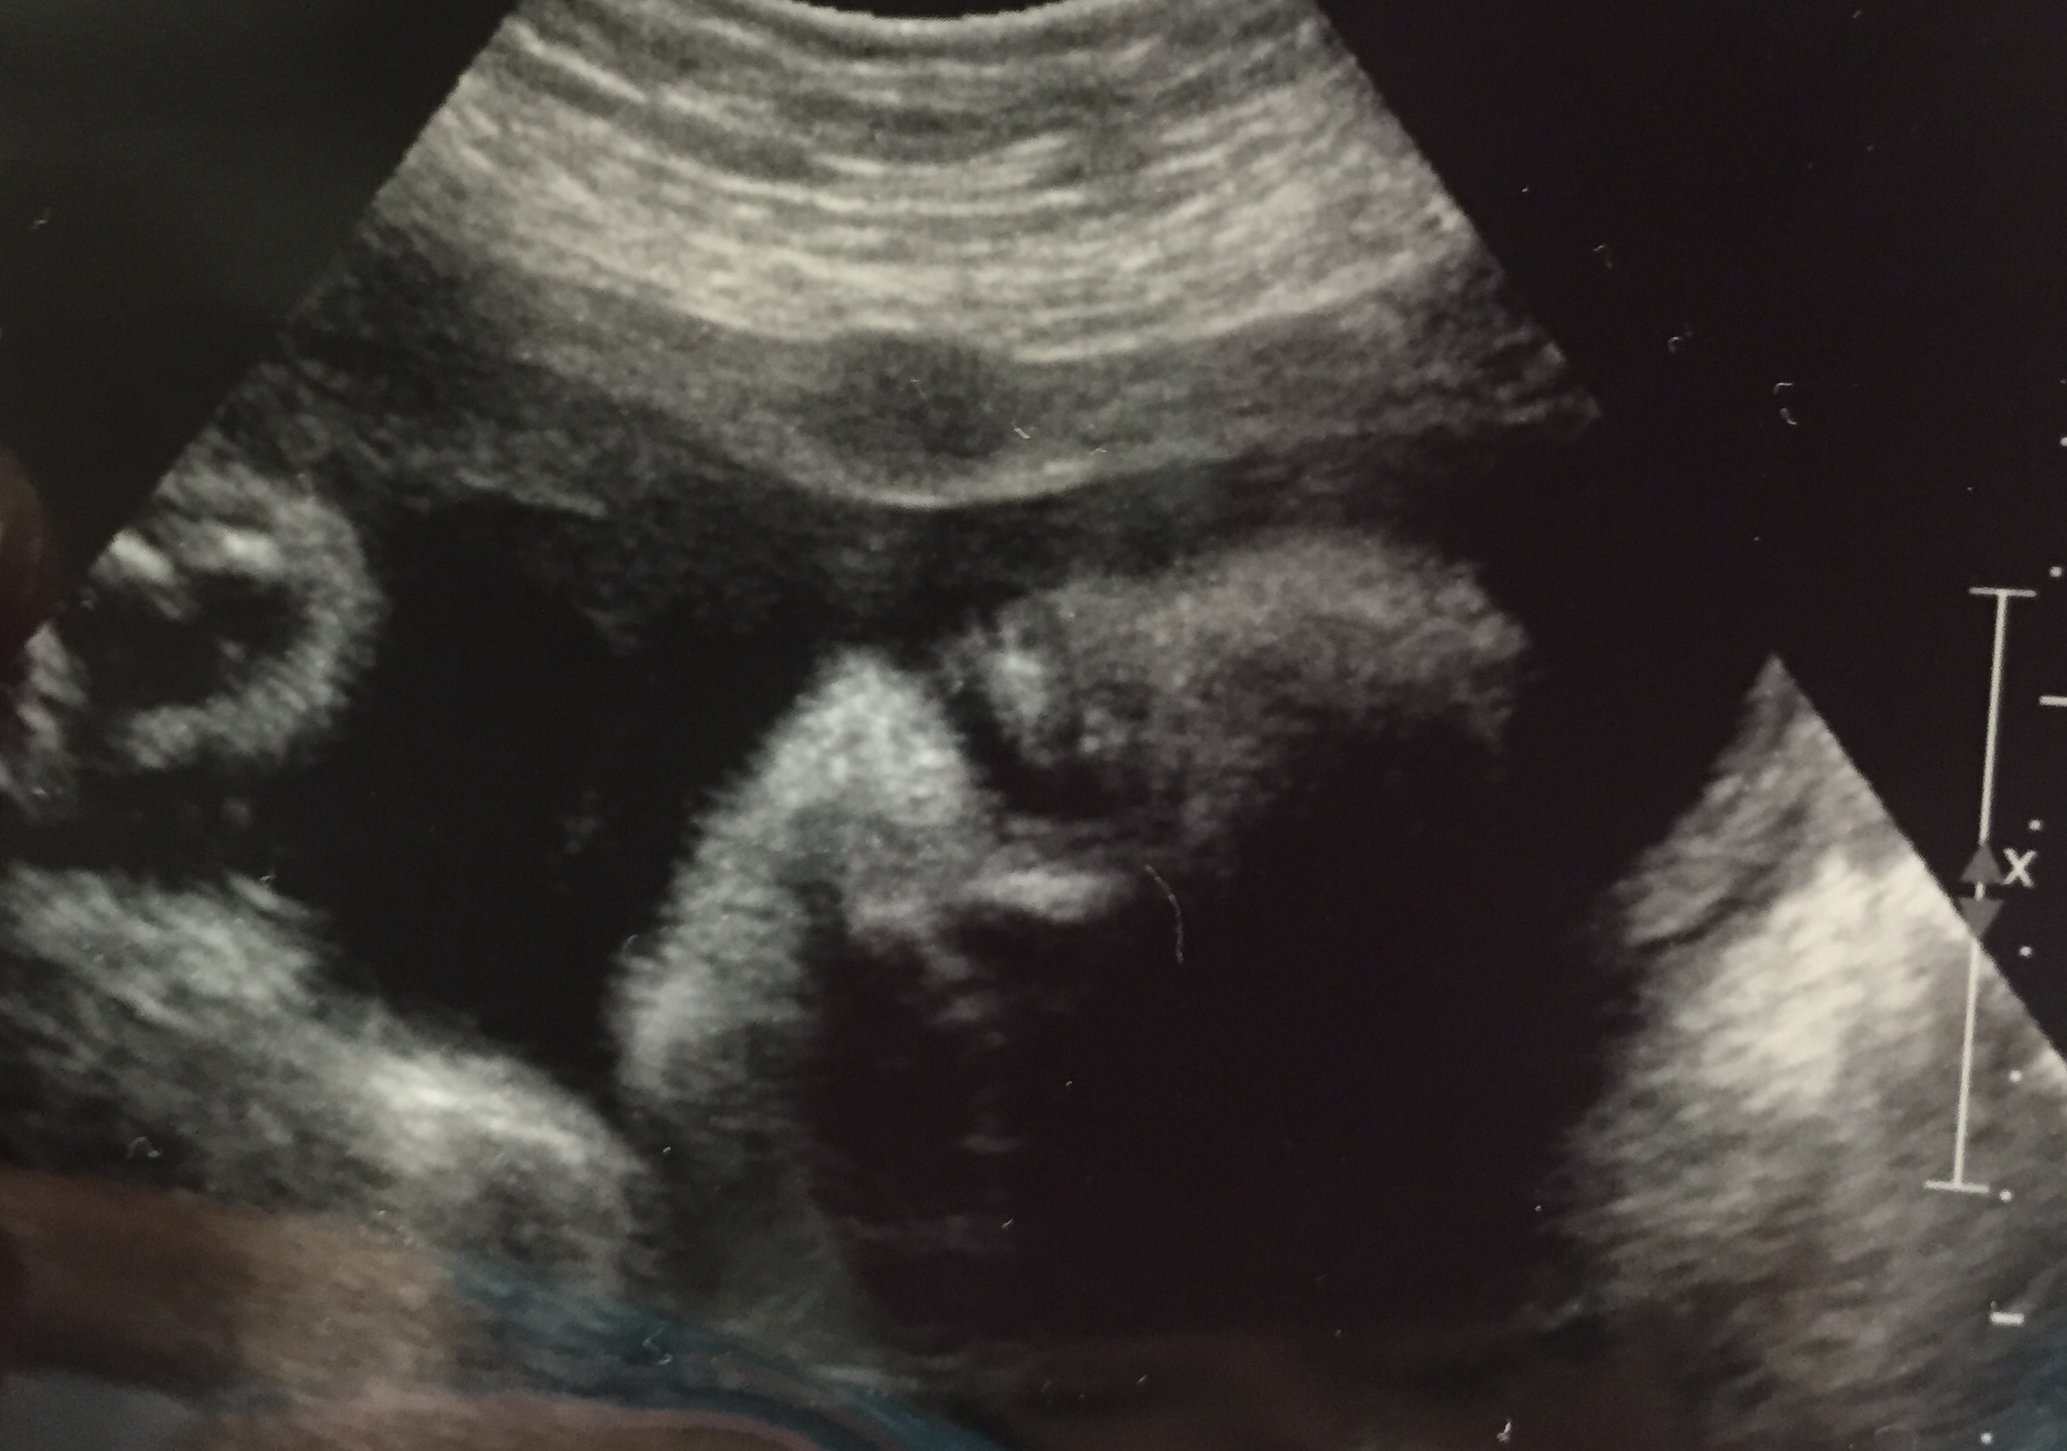

Can't believe I have a living breathing tiny human being inside of me! Baby was swallowing and putting hands on head. I also measured a week ahead! I also think I accidentally saw a penis when we are supposed to be team green! I am so excited!